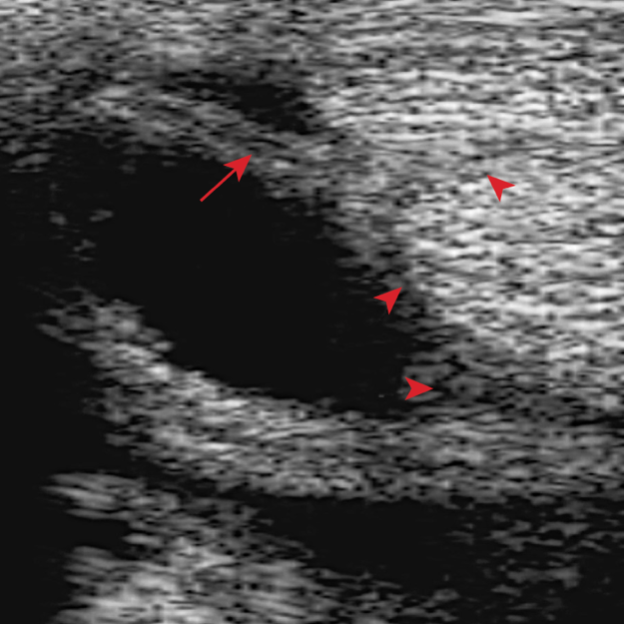

Upon further examination, contrast radiographs and ultrasound scans failed to identify any significant abnormalities apart from swollen synovium within the DFTS. To address this issue, our veterinary team administered 5mg of triamcinolone acetonide along with 20mg of HA, complemented by a compression wrap. Subsequently, the horse underwent a two-week confinement period in a small yard, followed by gradual reintroduction to exercise through 10 minutes of hand walking twice daily, with the distal limb wrapped for additional support.

However, when the condition resurfaced, our client chose to pursue tenoscopy, which fortunately revealed no clinically significant abnormalities. Following the procedure (2-weeks post-surgery), 2ml (50mg) of Arthramid was injected into the sheath, followed by two weeks of hand walking and a seamless transition back to regular riding activities.